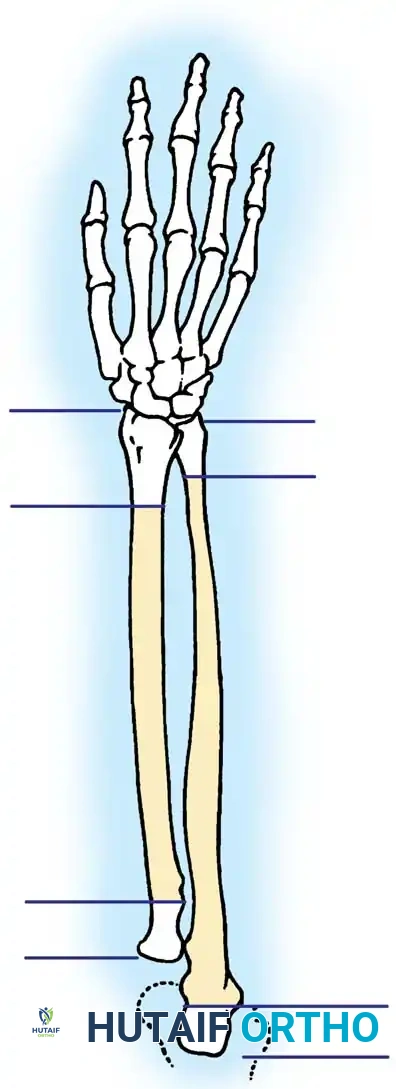

RADIUS AND ULNA: OPERATIVE PRINCIPLES

Fractures of the forearm bones in adults frequently demand surgical intervention to restore the complex biomechanics of the upper extremity. Surgical indications encompass fractures of the olecranon, the head or neck of the radius, and the proximal third of the ulna associated with dislocation of the radial head (Monteggia lesions). Furthermore, operative management is routinely indicated for isolated displaced fractures of the ulnar or radial shafts, as well as diaphyseal fractures involving both bones.

The primary goal of surgical intervention in the forearm and elbow is the exact restoration of anatomical alignment, axial length, and rotational stability. In the proximal ulna, the olecranon forms the greater sigmoid notch, articulating with the trochlea of the humerus. Any disruption here not only compromises the extensor mechanism but also threatens the intrinsic stability of the elbow joint.